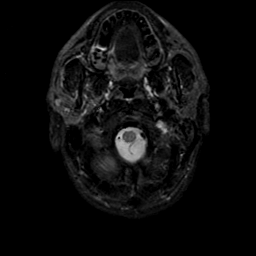

MR Study #9, April 14, 1991 -- Slice #2